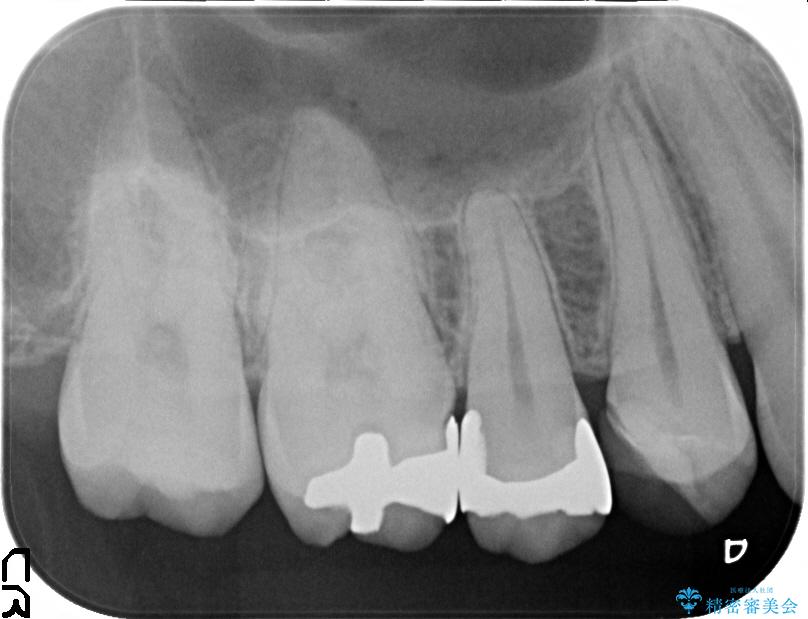

治療前

銀歯を除去してのセラミック治療[ メタルフリー ] 治療前画像 銀歯を除去してのセラミック治療[ メタルフリー ] 治療前画像 銀歯を除去してのセラミック治療[ メタルフリー ] 治療前画像